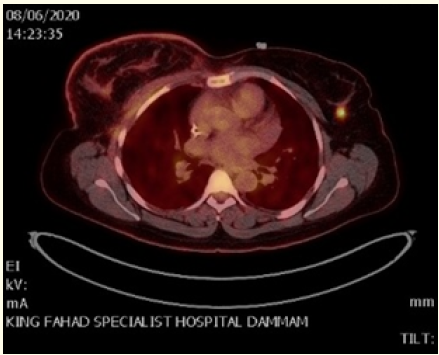

Case Report

The First Case Report of Neuroendocrine Tumor of the Breast with Metachronous Invasive Mammary Carcinoma

Mohammed Al Duhileb, Nadeen AlMushcab, Ayedh Al Qarni, Shakir I Shakir, Alaa Nour and Jamila AlAzhri. 5(10): 72-80.